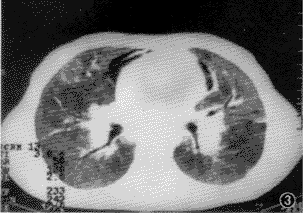

2.例2 男,12岁。致纤维化肺泡炎。入院时HRCT片显示出肺内同时存在磨玻璃样阴影、囊泡样改变和纵隔积气等(图3),符合该病在同一肺组织内可同时存在不同时期病变征象的HRCT表现特点,经激素治疗3个月后复查,磨玻璃影减少,纵隔积气消失(图4)。

图3 例2胸HRCT片 特发性肺纤维化改变:两肺透亮度减低,可见纵隔积气、磨玻璃征及小泡样气肿

图4 例2治疗3个月后的胸HRCT片 肺野透亮度增高,纵隔积气及磨玻璃征消失